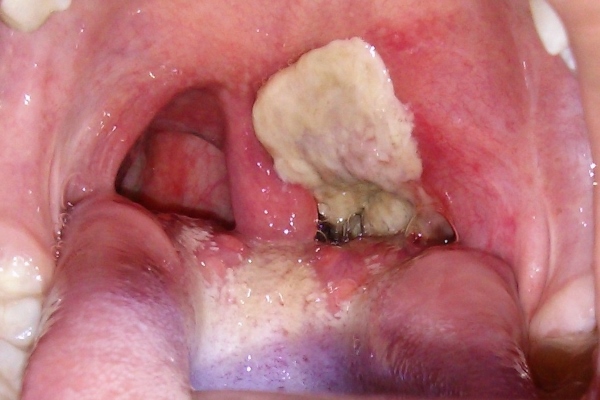

اقرأ المزيدالعمانية: حذرت دراسة جديدة أجراها باحثون من جامعة ملبورن في استراليا من أن استئصال اللوزتين في مرحلة الطفولة يزيد من...